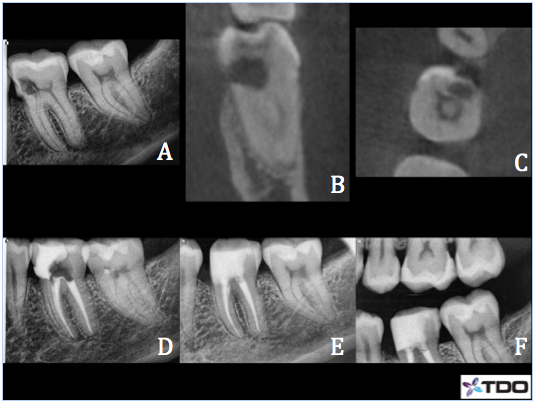

Case 2– #8 Class III ECIR with internal repair

62 y/o female presented complaining of biting tenderness and cold sensitivity. CBCT sagittal (B), coronal (C), and axial (D) slices showed a well defined cavernous ECIR lesion with a large lingual perforation. The lesion also communicated with the pulp. Apical PDL space is thickened. Prognosis is guarded however patient was very motivated to save the tooth at all costs. Recommend RCT followed by a surgical repair of the ECIR lesion. Pulpectomy was completed and Ca(OH)2 packed into the pulp system. The patient returned a few weeks later and RCT was completed. I was able to debride the ECIR defect very well via the lingual access and did not find it necessary to raise a surgical flap. I placed a cotton pellet with 90% trichloracetic acid over the resorbed area after prepping to burn out any remaining clastic cells. Geristore was used to fill in the defect and lingual access. Recall not yet available.